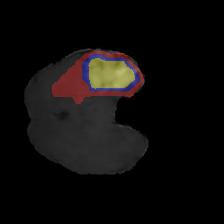

Brain tumor segmentation. Segmenting tumors in brain is challenging due to the high variance in appearance and shape of the tumors [28]. We use a subset of the 2017 Brain Tumour Image Segmentation (BraTS) dataset [29, 26]. It contains multi-parametric 3D MRI scans. The segmentation masks include (possibly overlapping) three classes of tumor. The 3D scans are split into 2D image slices, and only images that contain at least one tumor class are retained. Figure 7 shows three MSGNet generated samples as well as the corresponding masks. Since MSGNet adheres to the underlying relationships between various classes, we see that the generated images and the masks for different tumor classes are in line with the images and masks from the training set. In general, MSGNet rarely generated erroneous samples; we found roughly one sample per 3000 generations that could be rejected. Similar to the malaria experiment, we observed an improvement of 3.1% () in -score on the validation set.

A subset of the BrATS dataset was used. We used the images accompanied by segmentation layouts from the FLAIR and T1Gd modes. The segmentation layouts showed the sub-regions for three different classes: GD-enhancing tumor, the peritumoral edema, and the necrotic and non-enhancing tumor core. The brain and the background were treated as an additional class. We refer to [32] for further details. For the two modes, the background has been modelled using two different classes. We only considered half of the 155 slices, i.e., we took only the even-numbered slices and out of those we discarded the slices that did not include one of the previously mentioned tumor-classes in order to create a more balanced dataset. This resulted in 20,000 images that were further augmented with 6,000 MSGNet generated images. Example generations of the masks as well as the images are shown in Figure 12.